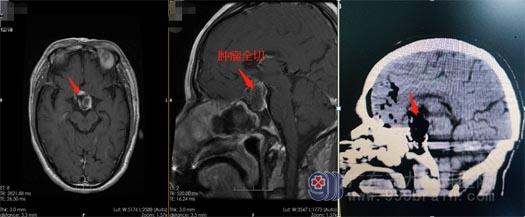

吴先生及家人充分了解病情后,同意手术治疗。神经外五科手术团队为吴先生行“内镜经鼻蝶鞍区占位切除术+颅低重建术”,术中发现肿瘤大小约为27mm×21mm×41mm,严重压迫视交叉、视神经,并且周边血供丰富,为手术带来了极大的困难;在手术医生的密切配合下,凭借着丰富的手术经验和先进的仪器设备,将手术顺利完成,术中出血量少,在全切肿瘤的同时保留了垂体功能。术后,吴先生的病情得到了很大改善,视力也开始逐渐恢复。

▲术后